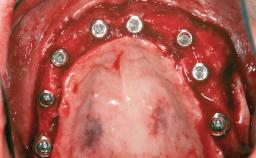

# of Implants 12

Type of Implants One-Piece|Reduced-Diameter

Bone Augmentation Horizontal|Staged

Augmentation Materials Autogenous chips|Autogenous block(s)|Membrane

Bone Volume Deficient horizontally, requiring prior grafting